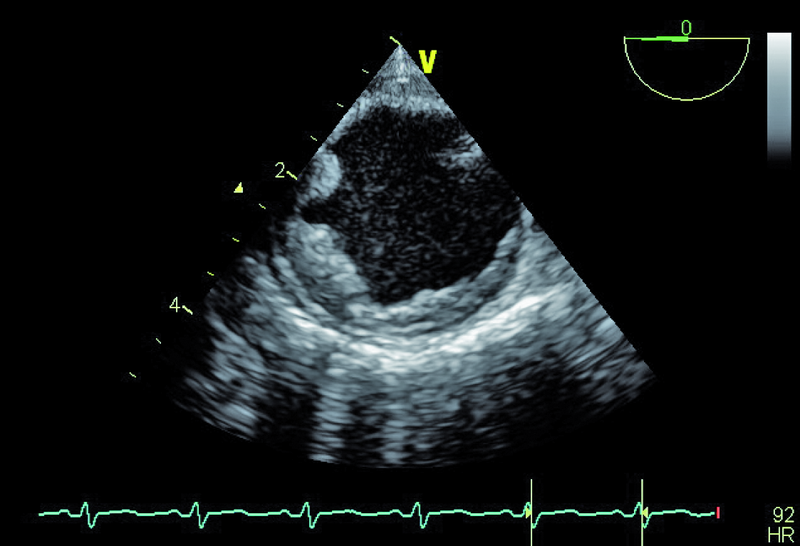

Czy zamieszczone ryciny mogą wskazywać na przyczynę udaru mózgu? Jak należy postąpić w przedstawionej sytuacji?

Wiek pacjenta, palenie tytoniu oraz chwiejne nadciśnienie tętnicze nakazują wykluczyć a priori tzw. kryptogenny udar mózgu. Przegroda międzyprzedsionkowa u chorego była szczelna, choć w badaniu przezprzełykowym (TOE) opisano śladowy kanał przetrwałego otworu owalnego (PFO), bez przechodzenia kontrastu ze strony prawej na lewą. Badanie przezprzełykowe pozwoliło także wykluczyć skrzeplinę w jamach serca (ryc. 1 – uszko lewego przedsionka) oraz istotne zmiany organiczne zastawki aortalnej (ryc. 2, 3). Prawdopodobną przyczyną udaru były nasilone zmiany miażdżycowe w łuku aorty z towarzyszącymi owrzodzeniami ściany naczynia (ryc. 4, 5). Warto zaznaczyć, że zmiany będące zgrubieniem błony wewnętrznej bywają dynamiczne i nie można wykluczyć powstawania ruchomych składowych (skrzeplin) na dużych elementach owrzodzenia. W diagnostyce miażdżycowego uszkodzenia aorty metodą z wyboru jest badanie przezprzełykowe, pozwalające zidentyfikować dzięki wysokiej rozdzielczości obrazu drobne, nawet kilkumilimetrowe owrzodzenia. Warto zaznaczyć, że badanie przezklatkowe nie dostarcza tak wyraźnego i jednoznacznego obrazu (ryc. 6). Korzyść z badania echokardiograficznego jest bez wątpienia większa niż z badania TK czy MR, ze względu na możliwość oceny ruchomości blaszek w czasie rzeczywistym. W rutynowej ocenie zwraca się uwagę na grubość blaszki miażdżycowej, obecność owrzodzeń, zwapnień oraz nałożonych ruchomych ech odpowiadających skrzeplinom – stanowiących tzw. potencjał zatorowy blaszki. Uważa się, że średnica blaszki przekraczająca 4 mm ma większy potencjał zatorowy niż owrzodzenie płytkie (w przedstawionym przypadku średnica blaszki wynosiła 7 mm). Dowiedziono ponadto, że w przypadku blaszek nieuwapnionych – jak w opisanej sytuacji – ryzyko zatoru jest większe niż w przypadku blaszek uwapnionych. Leczenie antykoagulacyjne w takim wypadku jest uzasadnione. Konieczne jest także włączenie dużej dawki statyn mimo braku zmian miażdżycowych w tętnicach wieńcowych (wykonano koronarografię). Ocena układu krążenia u pacjenta po przebytym incydencie zatorowym do OUN powinna być kompleksowa i powinna uwzględniać wszystkie możliwe nieprawidłowości.